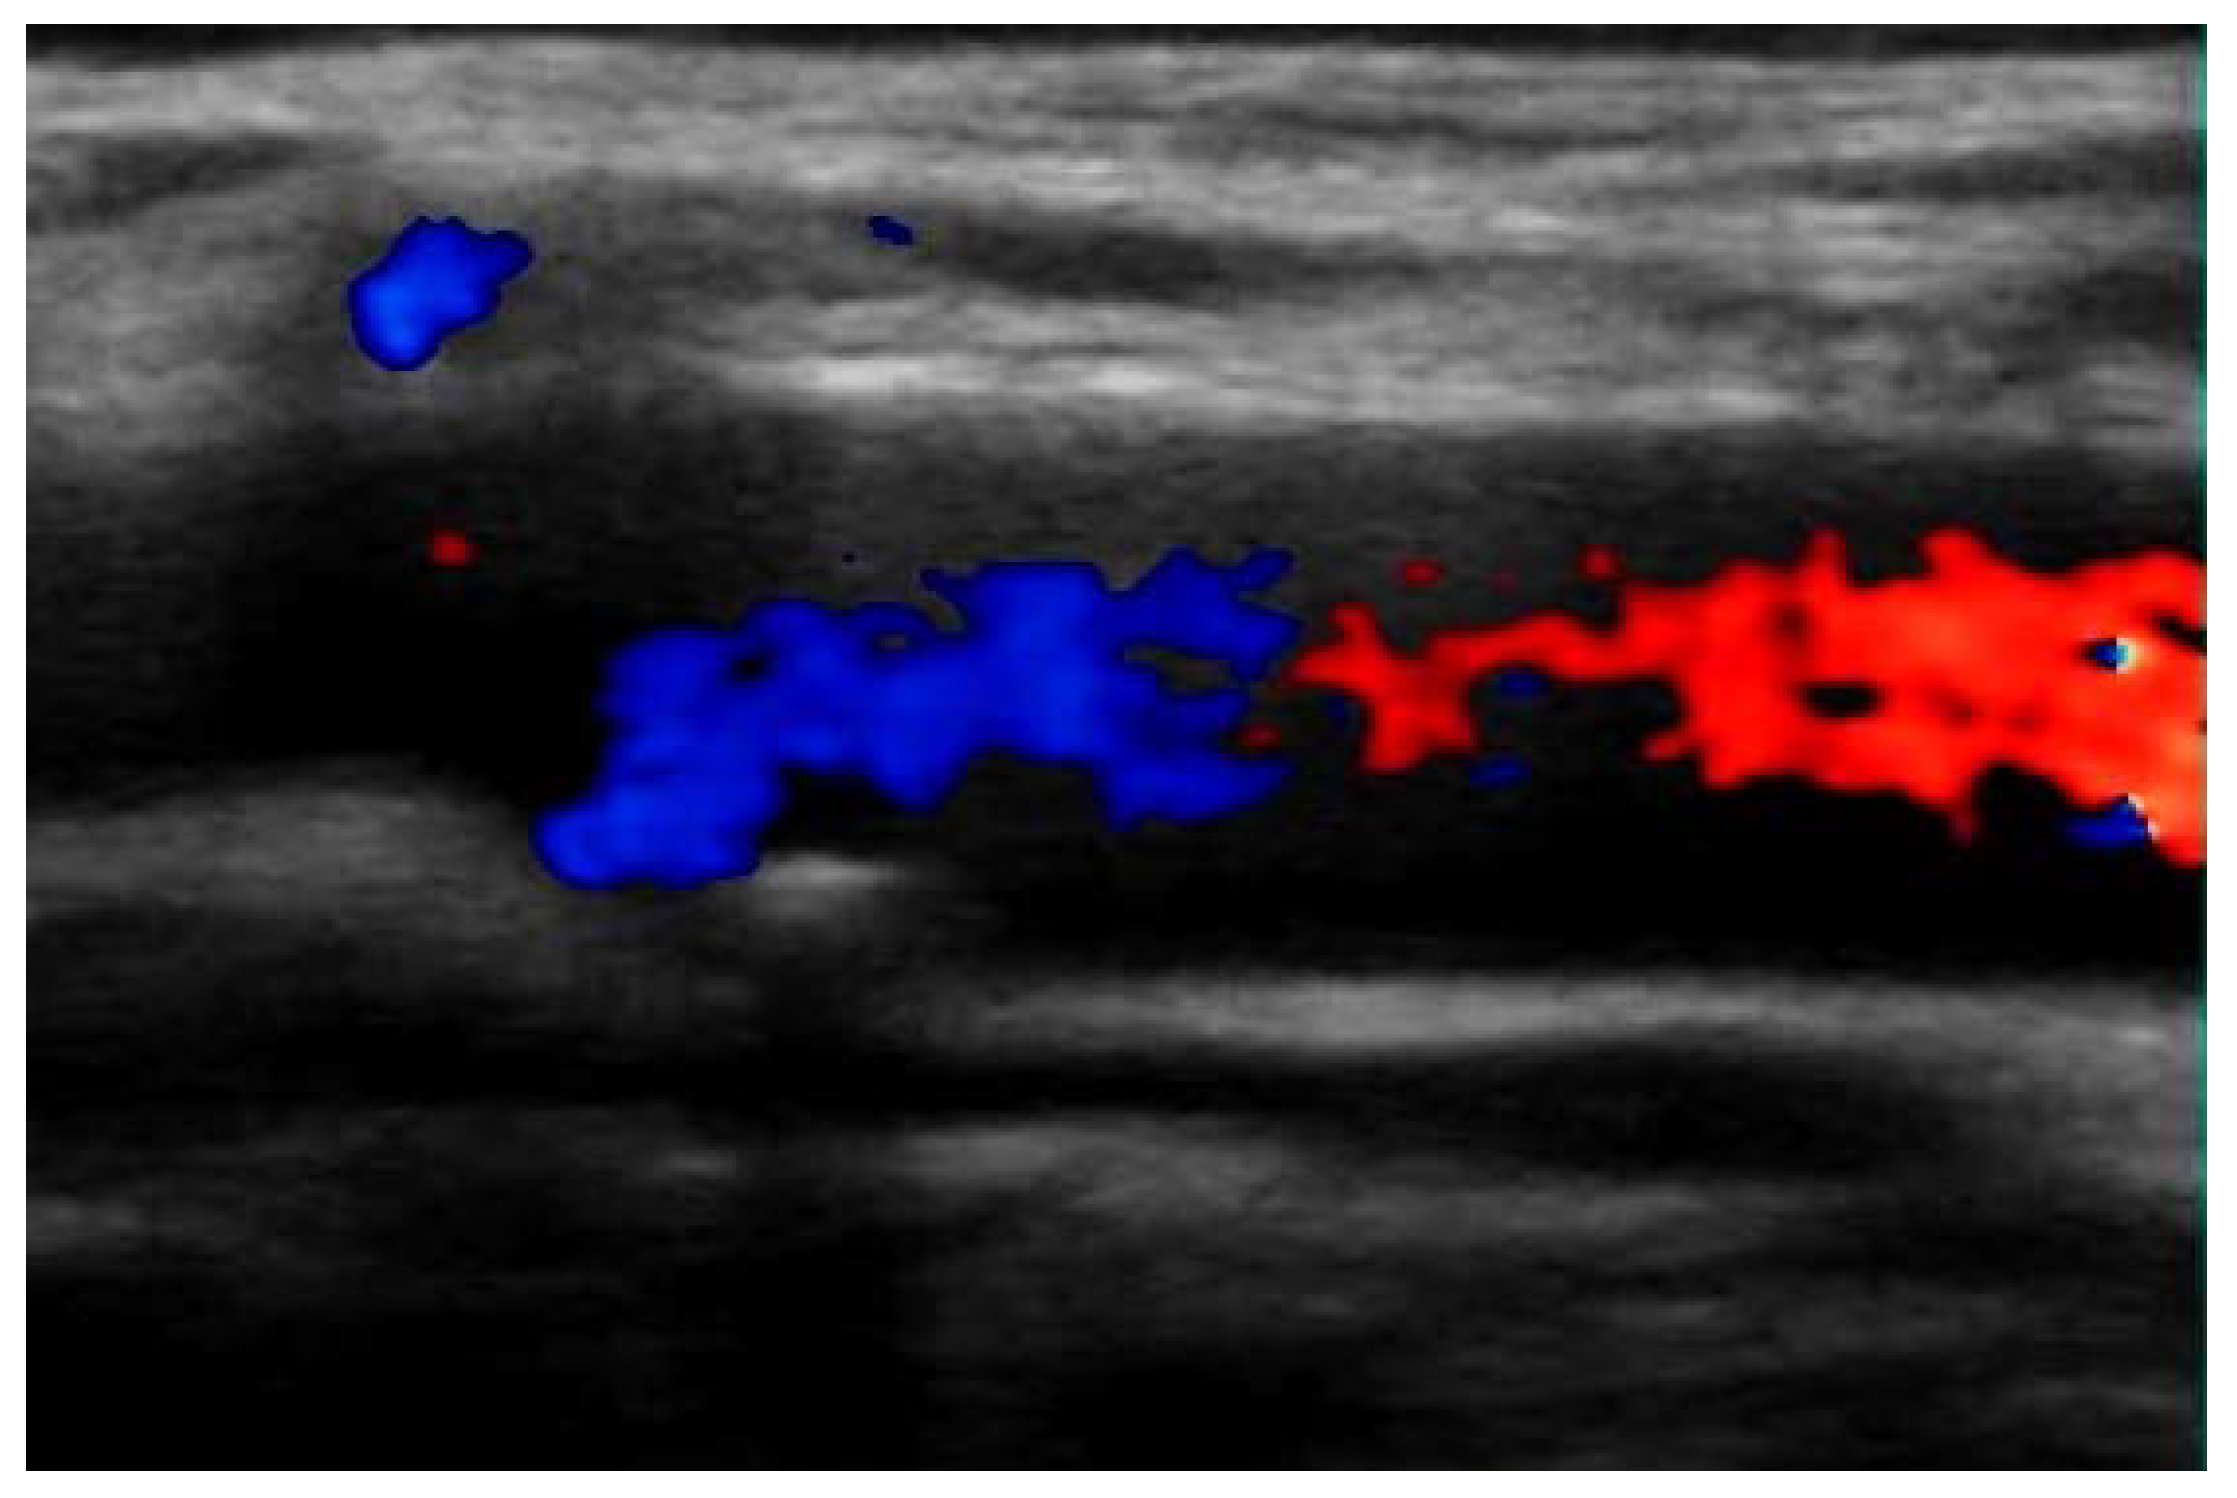

2. Case Presentation